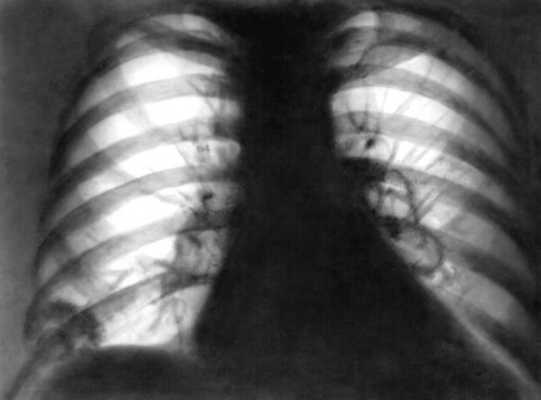

В легких появляются единичные или множественные инфильтраты с быстрым распадом и образованием полостей (рис. 2). Клиническая симптоматика зависит от локализации и распространения процесса: больные жалуются на кашель. Иногда надсадный, кровохарканье, одышку. У 5—20% больных изменения в легких является первым симптомом, у большинства же больных они появляются вслед за поражением верхних дыхательных путей. Поражение почек проявляется обычно протеинурией и микрогематурией, у некоторых больных развивается артериальная гипертензия. Могут отмечаться изменения кожи в виде различных (геморрагических, язвенных, узелковых) высыпаний, артралгии преимущественно крупных суставов. Возможно поражение глаз вследствие распространения гранулематозного процесса на орбиту глаза с развитием экзофтальма.

Рентгенограмма легких: инфильтрат над диафрагмой справа, две полости распада в области левого корня">

Рис. 2. Рентгенограмма легких: инфильтрат над диафрагмой справа, две полости распада в области левого корня.

На рентгенограммах легких выявляются инфильтраты, имеющие иногда «летучий» характер, с образованием полостей до 5 см в диаметре (фибринозно-гнойная пневмония с некрозом). Обширные инфильтраты легочной ткани с большими полостями распада - характерный рентгенологический признак гранулематоза Вегенера.